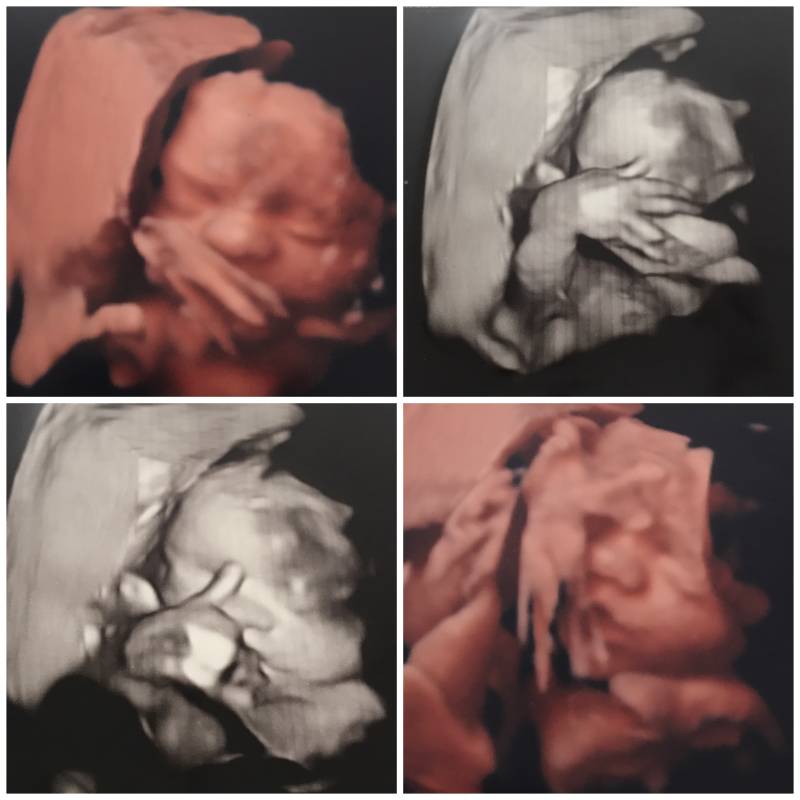

Over 2 dagen wordt Benjamin alweer 1 jaar. Ik zal alvast wat vertellen over onze eigenwijze knul, en eigenwijs is hij zeker! Vanaf 20 weken lag hij namelijk al in stuit, en ondanks dat de verloskundige toen zei dat hij nog genoeg tijd had om te draaien, wist ik al dat dat niet ging gebeuren! Hij schopte altijd op dezelfde plek en je kon heel goed voelen waar zijn voetjes, hoofdje en kontje lag. De weken verstreken en uit de echo’s kwam telkens hetzelfde, Benjamin lag keer op keer in onvolkomen stuit. Dit betekende dat wij vanuit de verloskundige werden overgeheveld naar de gynaecoloog om daar de laatste checks te krijgen voordat onze kleine man geboren zou worden! Met 35 weken werd ik gezien door een gynaecoloog, en hebben wij besloten dat we gingen proberen om Benjamin te draaien, dit kon gelukkig dezelfde dag nog gebeuren. Met zweethanden en knikkende knieën lag ik daar dan, aan de ctg om te kijken of alles nog goed met hem ging. Ik kreeg weeënremmers omdat bij een uitwendige versie de baarmoeder hard wordt, en hij moet juist zo ontspannen mogelijk zijn om het kind te kunnen draaien. Na een aantal minuten waren de weeënremmers ingewerkt en konden ze beginnen. 1 gynaecoloog en 1 verpleegkundige stonden aan het bed. De gynaecoloog probeerde haar hand onder het kontje te krijgen en de verpleegkundige had Benjamin zijn hoofdje vast, toen begon het draaien. Voor de mensen die dit nooit meegemaakt hebben: geloof me, dat wil je ook niet. Het is absoluut geen pretje en de kracht die zij er op loslieten was niet geruststellend, voor mijn gevoel kon dit nooit goed voor een kind zijn. Na meerdere pogingen moesten zij helaas opgeven, Benjamin lag al te ver ingedaald en ze kon helaas niet met haar hand onder zijn kontje komen, die dus al ver in het bekken lag. Wij werden terug naar huis gestuurd met een keuze. Benjamin kon gehaald worden met een keizersnede, wat veel risico voor mij zou zijn, of ik kon proberen natuurlijk van hem te bevallen, maar dat laatste zou weer veel risico’s voor hem meebrengen. In een normale situatie zou ik direct voor een keizersnede gekozen hebben alleen was dit geen normale situatie. Door een eerdere operatie kon ik namelijk geen ruggenprik krijgen wat betekende dat ik volledig onder narcose zou moeten en dus niks van de geboorte van Benjamin mee zou krijgen, een onmogelijke keuze dus. Later bleek dat ik geen keuze meer had.